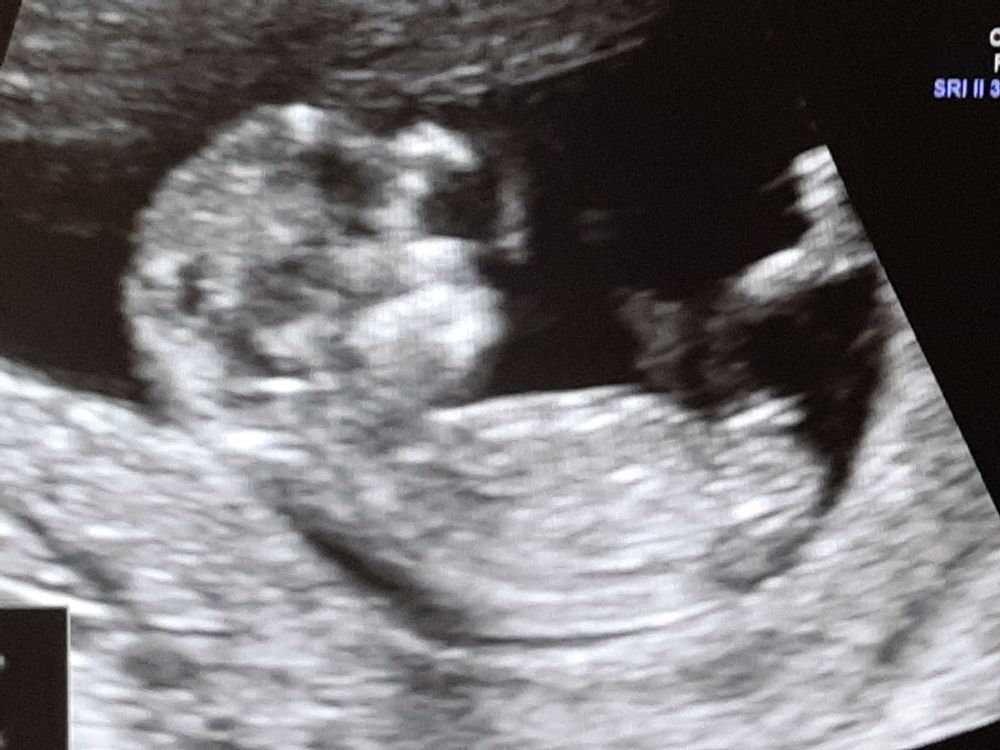

Как же я переживала. Это не передать. В прошлом зб на 8-9 неделе. Тогда я даже на учет встать не успела. В этот раз встала на учет,получила обменную карту, направление на УЗИ-скрининг и анализы. За талоном на узи пришла 5го августа, должна была получить на 7 августа, но дали на сегодня. По времени 10.20, а зашла в 12.30. По узи все хорошо, все показатели и кровоток в норме. Пол пока не определили, я была голодная, малыш тоже и ленится перевернуться. Врач пыталась его расшевелить, а он руками и ногами возмущённо потряс и все) завтра сдам кровь скрининговую и сразу оак, оам, на ВИЧ, гепатиты, сифилис, группу (хотя я ее знаю), в пн сдам бак посев мочи. Еще надо контроль ттг и можно спокойно ехать в родной город к маме на юбилей) по узи опережает, кстати) по месячным сейчас 11+3, по узи 11+6 )) фото прикрепила

, может вы поймёте пол)